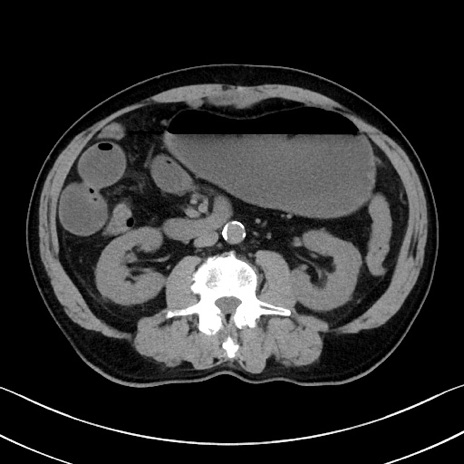

症例35(横断像)

【症例】70歳代 男性

【主訴】腹部膨満、嘔吐

【現病歴】昨日より腹部膨満感出現。本日増悪し、仙痛出現。嘔吐あり、受診。

【既往歴】糖尿病、胆摘後

【身体所見】BP 149/80mmHg、HR 74/min、BT 35.9℃、腹部:膨満、軟、圧痛なし。腸雑音減弱あり。上腹部正中切開瘢痕あり。

【データ】WBC 13500、CRP 1.72